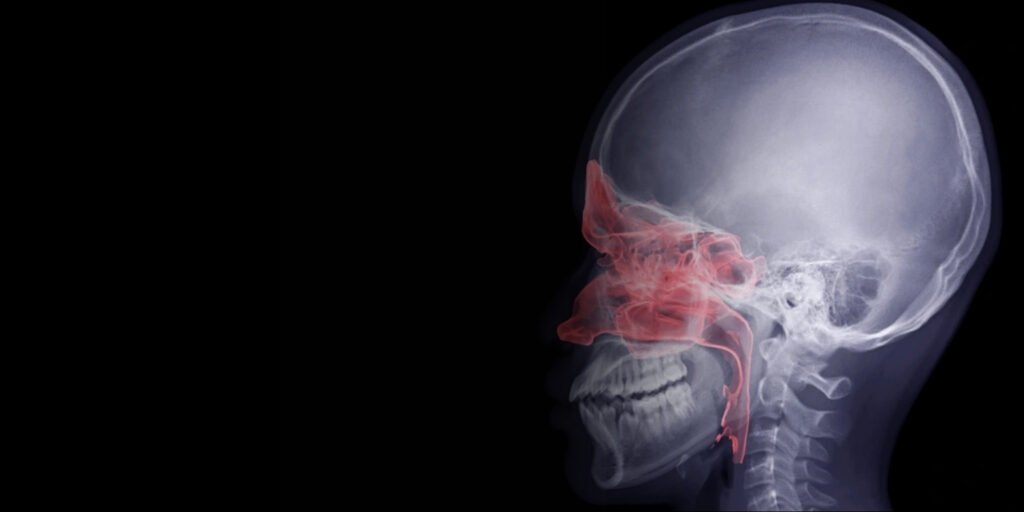

Skull base cancers are rare, complex tumors that grow at the bottom of the skull, involving critical areas such as the nasal cavity, sinuses, eyes, brain lining, and cranial nerves: their deep site and proximity to relevant structures make treatment very specialized in surgery and reconstruction.

Skull base cancer develops at the bottom of the skull, affecting critical nerves and structures. Symptoms often appear gradually and may impact vision, hearing, and facial function.